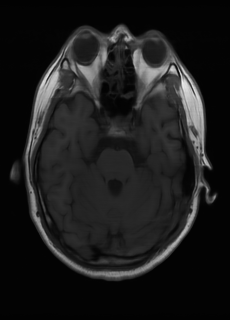

As we observe from the right image in Fig. 2, our BRM, both from MIMO and SISO settings, predicts the performance of dedicated models with a high correlation. We further choose the best three , and perform the last stage of fine-tuning accordingly to (6). A visual evaluation on real data is shown in Fig. 3. For simulated data, please refer to the Supplemental Material section.

Base on the best performing , we perceive that among , , and FLAIR, the results are best when is sampled the most. We suggest that this makes intuitive sense as images provide the best contrast out of the three sequences, which can compensate for the details lost in other images. The same observation can be made on the simulated data, where both and FLAIR show good contrast. When the time setting is changed to non-uniformity, we can see that our search for the best sampling strategy reflects the change. is sampled more as a result of faster acquisition time, while is still sufficiently sampled.

| Sequence | LR | SISO | MIMO | MIMO tuned | GT |

|---|---|---|---|---|---|

(a) 34.38/0.9371

(a) 34.38/0.9371

|

(b) 42.42/0.9883

(b) 42.42/0.9883

|

(c) 44.60/0.9920

(c) 44.60/0.9920

|

(d) 45.50/0.9940

(d) 45.50/0.9940

|

(e) PSNR/SSIM

(e) PSNR/SSIM

|

|

(f) 29.74/0.8903

(f) 29.74/0.8903

|

(g) 36.25/0.9734

(g) 36.25/0.9734

|

(h) 36.42/0.9752

(h) 36.42/0.9752

|

(i) 37.70/0.9832

(i) 37.70/0.9832

|

(j) PSNR/SSIM

(j) PSNR/SSIM

|

|

(k) 39.89/0.9311

(k) 39.89/0.9311

|

(l) 43.94/0.9864

(l) 43.94/0.9864

|

(m) 44.74/0.9883

(m) 44.74/0.9883

|

(n) 45.49/0.9894

(n) 45.49/0.9894

|

(o) PSNR/SSIM

(o) PSNR/SSIM

|